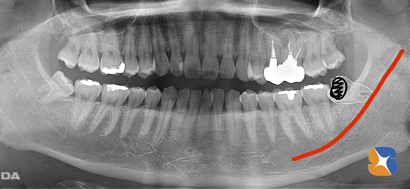

30代の男性。主訴は「親知らずを抜きたいが、正直恐くて放っておいた。しかし、ズキズキ痛み出してきたので覚悟はしている。ネットで探してここに来た。是非とも先生にお願いしたい」でした。

患者様の痛み、腫れ、恐怖を考慮して、静脈鎮静法(点滴麻酔)を行いながら、虫歯で崩壊した横向きの親知らずを抜くことにしました。

幸い短時間で抜歯は終了。ただし、抜歯あとの早期回復と痛みを軽減させるため、テルプラグ(無料)を入れて抜歯は終了しました。